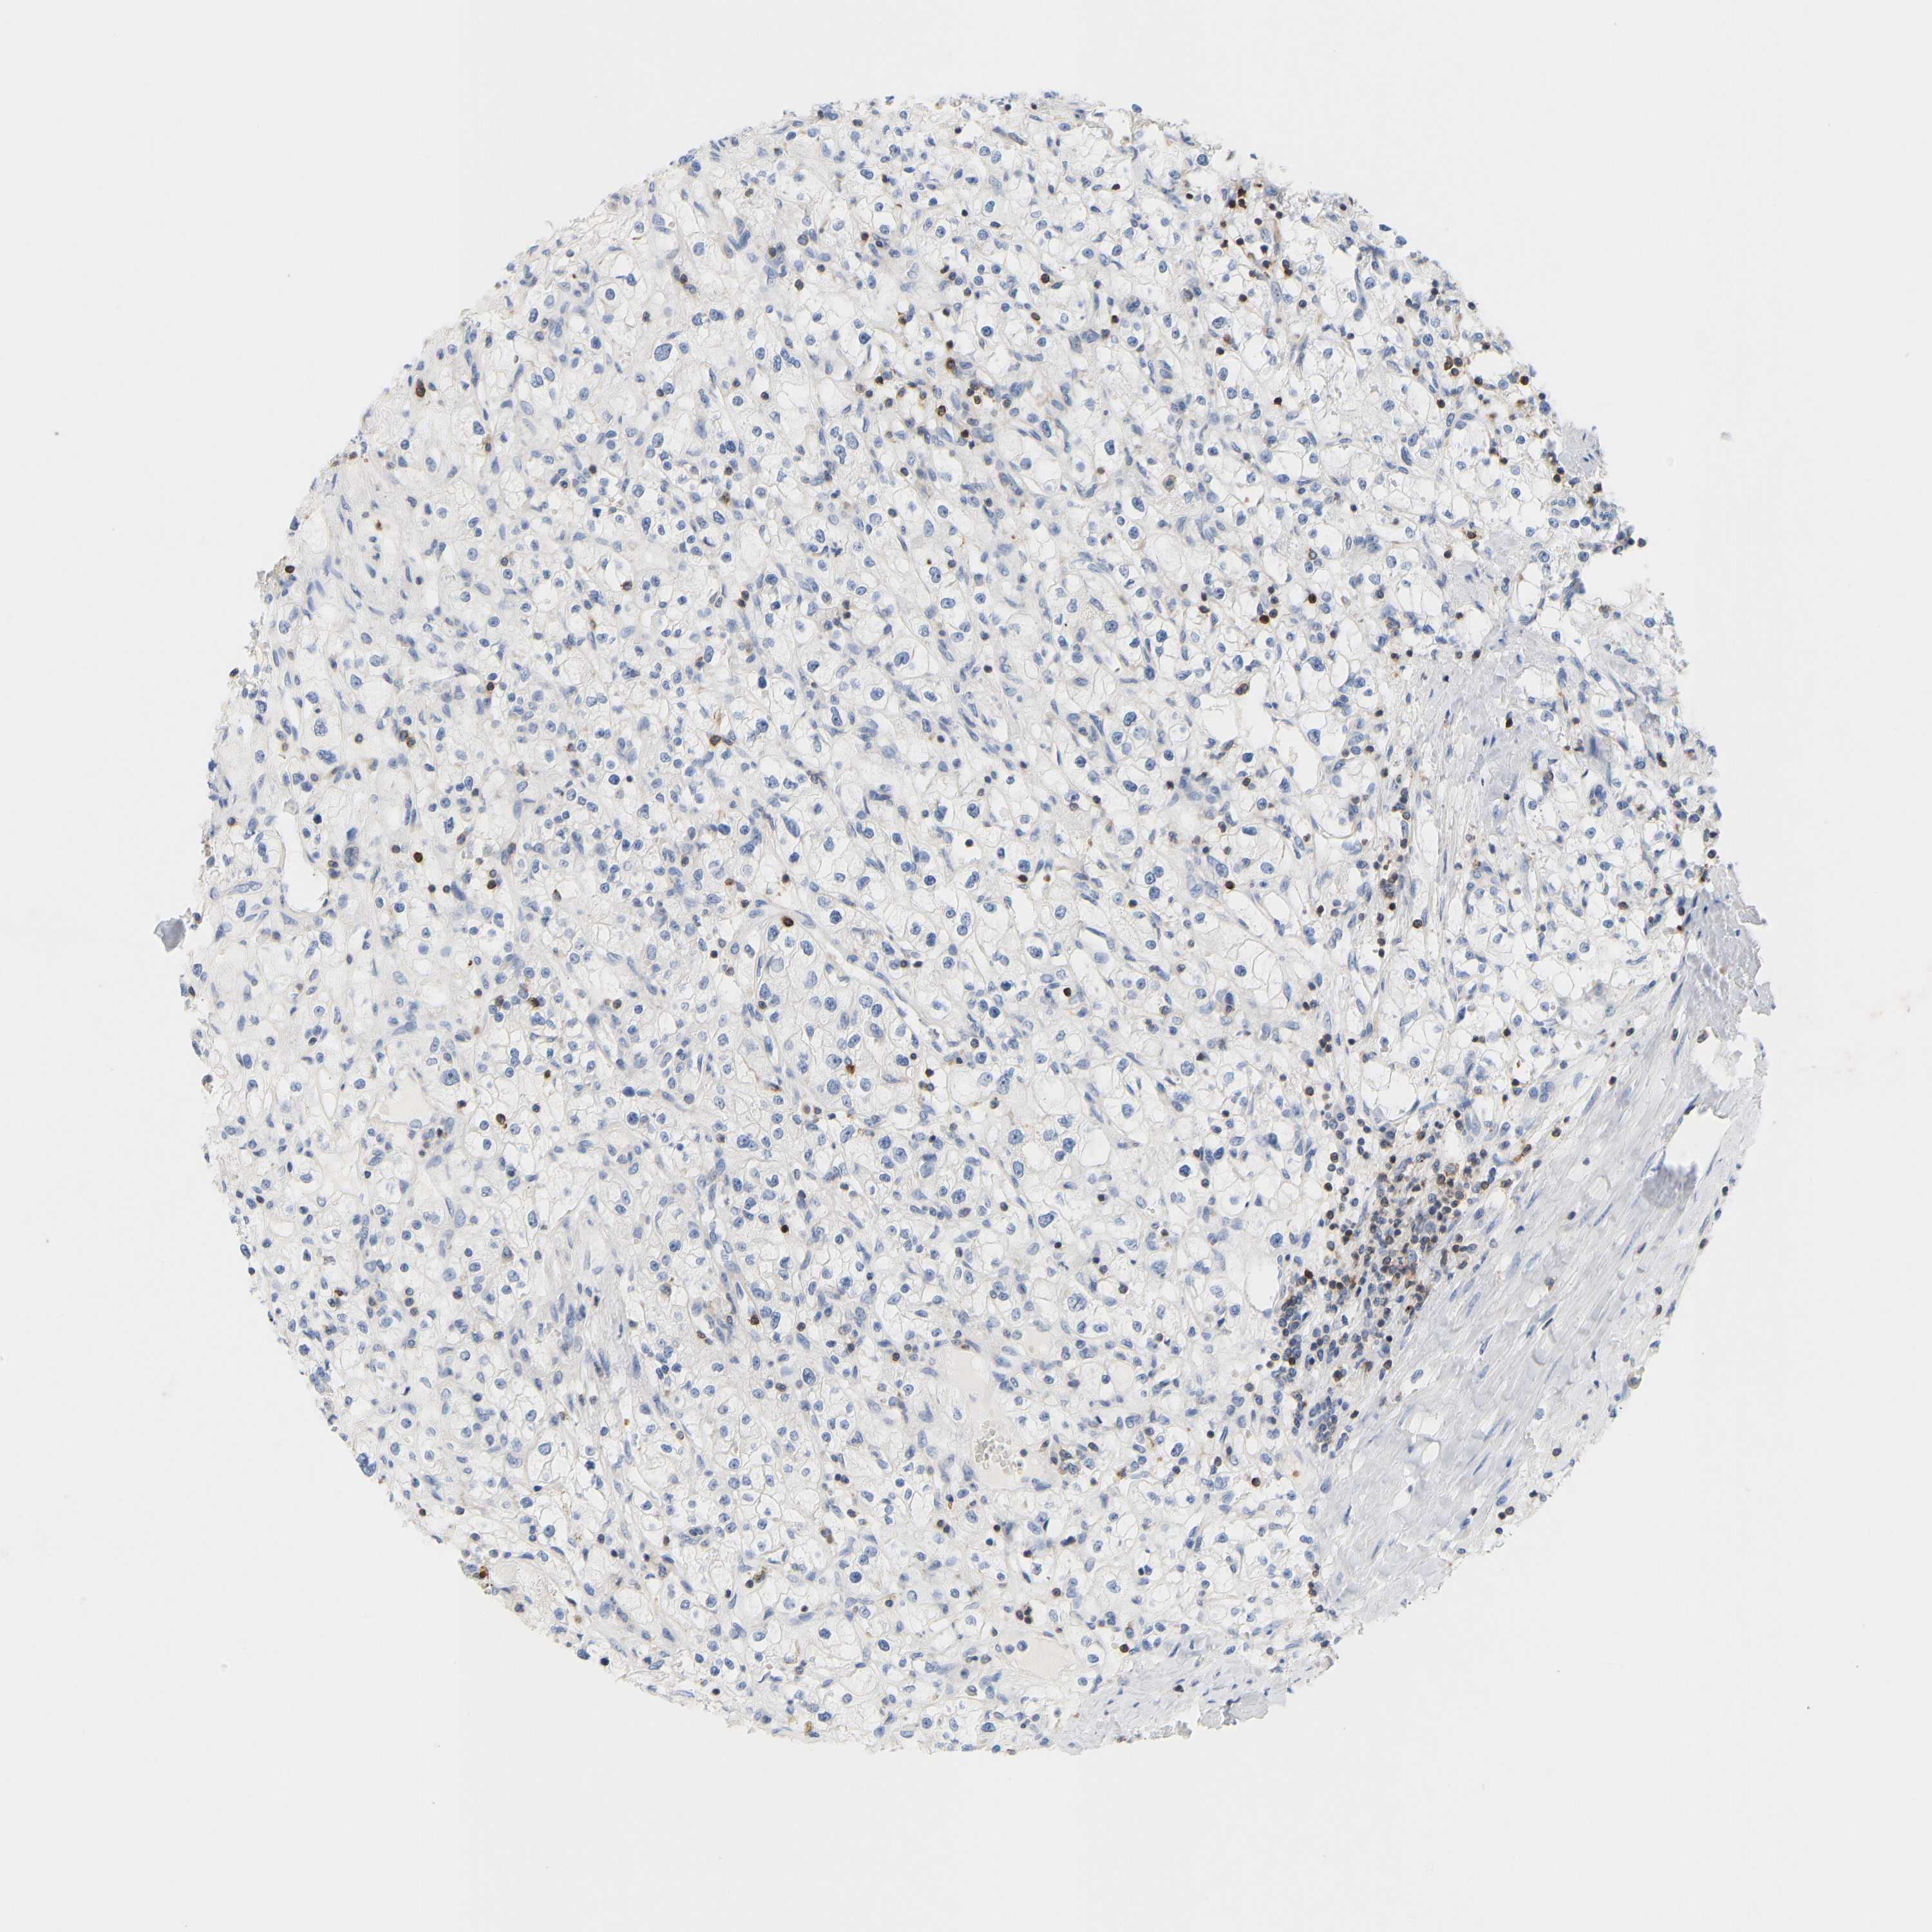

EVL is potential prognostic, high expression is favorable in Kidney Renal Papillary Cell Carcinoma (TCGA)